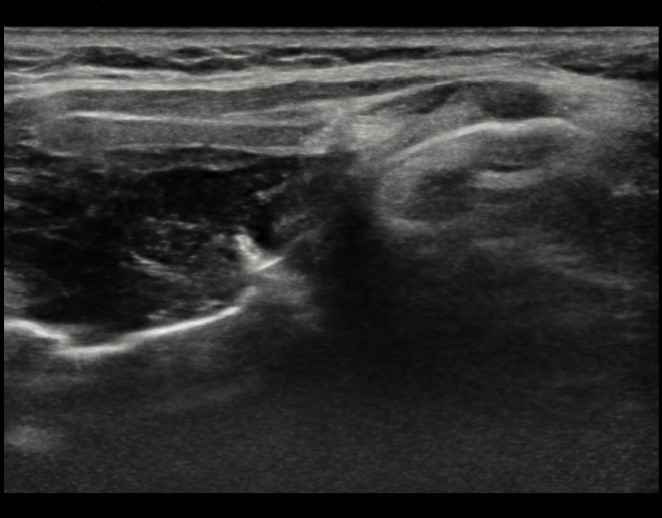

The lesion was readily visualized on ultrasound (Figures 4 and 5).

![]() |

Figure 4. Longitudinal image through larynx.

|